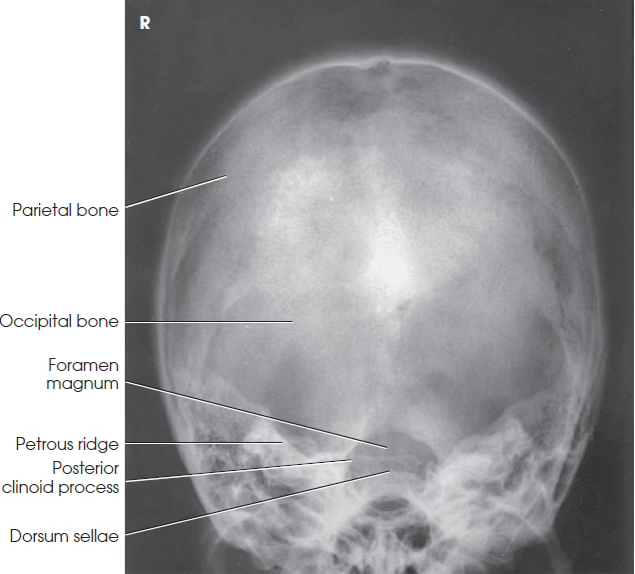

What view is this?

AP Axial (Towne) skull